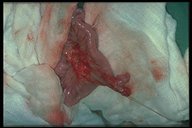

The perforation of an inflamed Meckel's diverticulum caused peritonitis and partial obstruction. Fibrin coated on the diverticulum is noted

A Meckel's diverticulum is found adherent to the anterior abdominal wall at umbilicus. The attached band (omphalomesenteric or Meckel's band) caused small bowel obstruction in this child

A resected specimen consisted of Meckel's diverticulum, omphalomesenteric band and some part of umbilicus